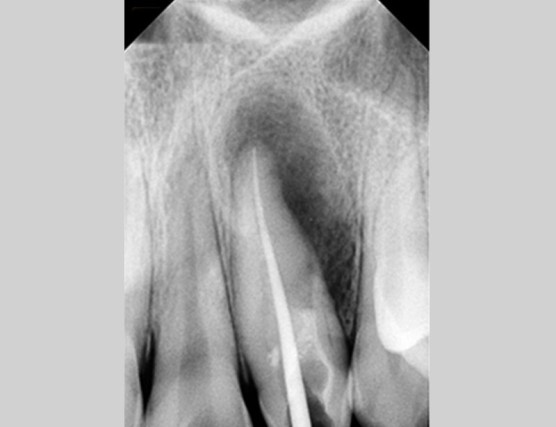

[2020.01.06 처음 내원 시 찍은 사진]

처음 내원했을당시의 사진입니다.

잇몸밖으로 여드름과 같이 농이 배출되고 있는 상황이었으며, 통증이나 증상은 없었습니다.